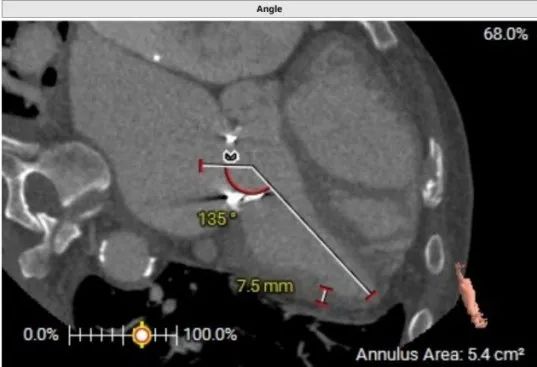

术前CT评估示:患者二尖瓣生物瓣置换术后,原生物瓣型号未知,生物瓣金属环平均内径25.9mm,外径31.5mm,瓣架高度15.9mm;

左心室和二尖瓣轴线角度:135°;

主动脉-二尖瓣角度:102.3°;